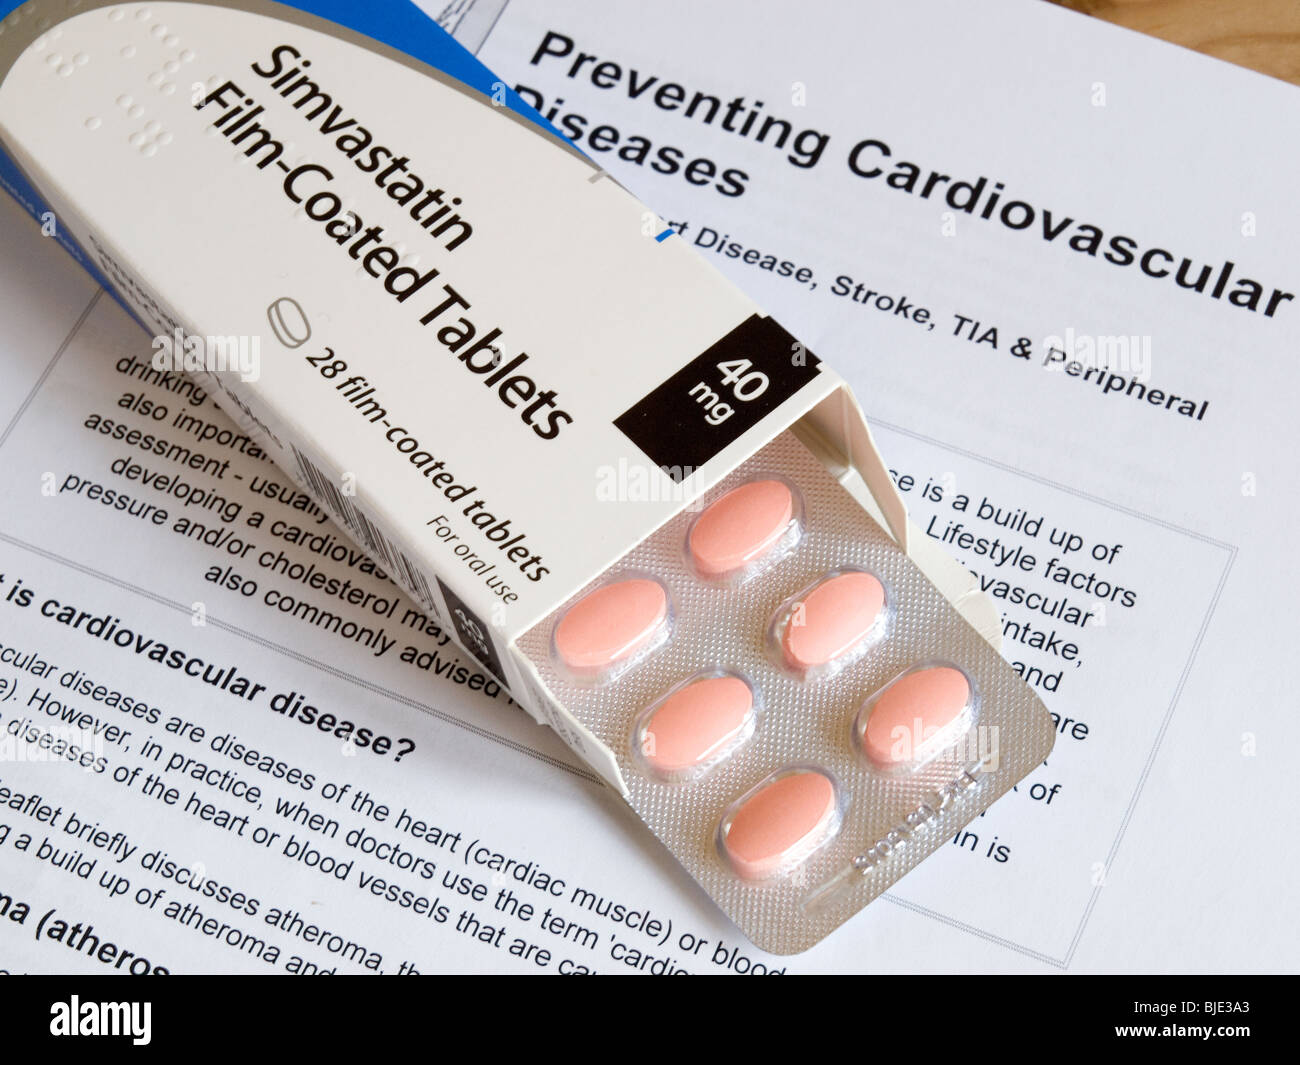

A box and a blister pack of Statin tablets on a leaflet about Cardiovascular heart disease Stock Photohttps://www.alamy.com/image-license-details/?v=1https://www.alamy.com/stock-photo-a-box-and-a-blister-pack-of-statin-tablets-on-a-leaflet-about-cardiovascular-28584139.html

A box and a blister pack of Statin tablets on a leaflet about Cardiovascular heart disease Stock Photohttps://www.alamy.com/image-license-details/?v=1https://www.alamy.com/stock-photo-a-box-and-a-blister-pack-of-statin-tablets-on-a-leaflet-about-cardiovascular-28584139.htmlRMBJE3A3–A box and a blister pack of Statin tablets on a leaflet about Cardiovascular heart disease